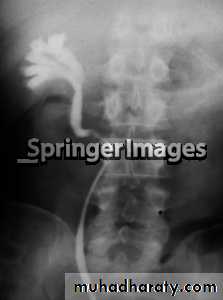

14- Retrocaval

16- Retrocaval